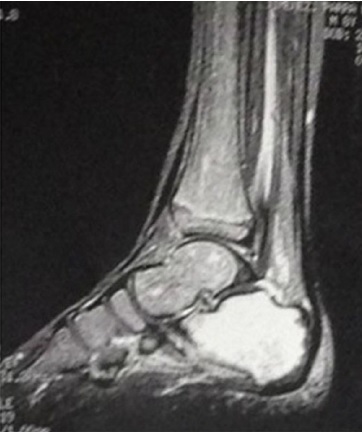

La resonancia es de mucha ayuda para evaluar alteraciones en médula ósea y tejidos blandos [7]. Se reporta una sensibilidad de 94%, con una especificidad del 85,5% [6]

La RM se realizó en 6 pacientes con hallazgos sugestivos de osteomielitis en 5 de ellos (Figura 3).

El papel de las imágenes es importante como parte del diagnóstico de la enfermedad. Los hallazgos de radiografía son muy inespecíficos y se presentaron en el 50% de los pacientes del estudio y orientaban hacia un proceso infeccioso en el 50% de ellos de forma clara. La resonancia magnética y la gammagrafía aportan información valiosa acerca de procesos infecciosos osteoarticulares. En los 6 pacientes de este estudio en los que se realizó la RM, 5 reportaron cambios compatibles con una infección del calcáneo. La resonancia tiene una sensibilidad y especificidad altas para el diagnóstico de la lesión.